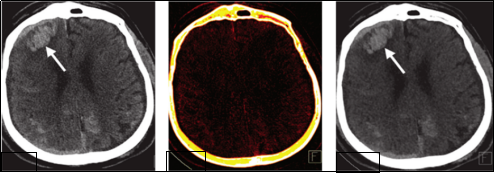

病例一:右侧额叶、双侧枕叶脑出血

图片1

(图像:虚拟平扫图显示高密度灶持续存在,碘叠加图未见碘染——证实为脑实质出血)